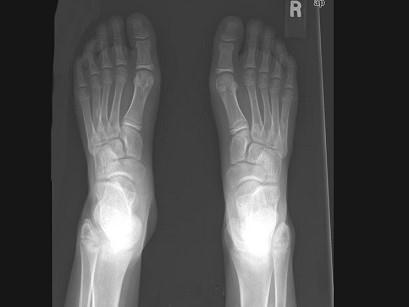

问题 女,12岁,脊柱侧弯畸形,双下肢长短不一,请结合影像图像,最可能的诊断是 ( )

选项 A、非骨化性纤维瘤 B、Paget病 C、骨巨细胞瘤 D、内生软骨瘤 E、骨纤维异常增殖症

答案 E